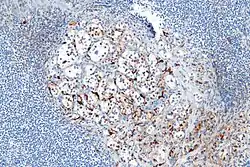

- Alrededor del 40% de los carcinoides tienen una dispersión de células sustentaculares, que se tiñen positivamente para S-100 .[6]